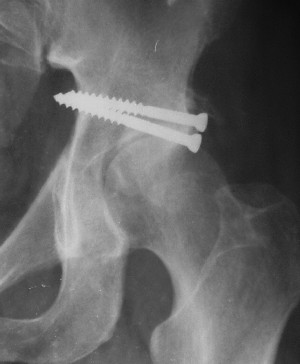

Контрольный снимок перед разрешением нагрузки прямой 13/10/03

Перед разрешением нагрузки боковой 13/10/03

Больной 18 мая 2003 года в автоаварии получил перелом левой вертлужной впадины, вывих бедра. Госпитализирован в один из стационаров области.Вывих вправлен. В последствии бедро вывихивалось еще дважды. На консультацию был представлен снимок от 19.05.03г., больной переведен к нам 3.06.03г. Снимок при поступлении - перелом впадины, задне-верхний вывих бедра. 05.06.2003 г. выполнено открытое вправление вывиха левого бедра и остеосинтез стенки вертлужной впадины двумя винтами. Послеоперационный период без осложнений. Объем движений в левом тазобедренном суставе восстановился полностью. Выписан на амбулаторное лечение в удовлетворительном состоянии с рекомендациями 3 месяца ходить на костылях без нагрузки на оперированную конечность. На контрольных рентгенограммах левого тазобедренного сустава 13.10.2003 г. - признаки консолидации перелома; плотность, форма головки и состояние суставных поверхностей удовлетворительные. Разрешена дозированная осевая нагрузка, на конечность с использованием дополнительной опоры. 19.12.2003 г. больной обратился с жалобами на боли в левом тазобедренном суставе. На рентгенограммах левого тазобедренного сустава 19.12.2003 г., 20.02.04г. - асептичекий некроз головки бедра. 5.04.04г. - эндопротез. Сейчас ходит без трости, не хромает. Особенность эндопротезирования - при удалении винтов прослежена линия перелома заднего края впадины и предложено установить чашку несколько меньшего диаметра, чтобы она была покрыта несломанной частью.